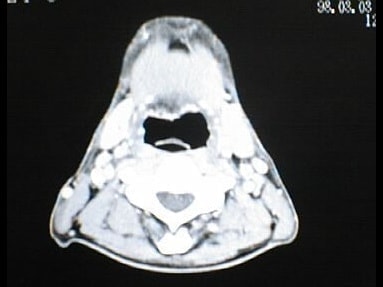

CT画像比較

入院当時CT画像①

入院3か月後癌消滅CT画像①